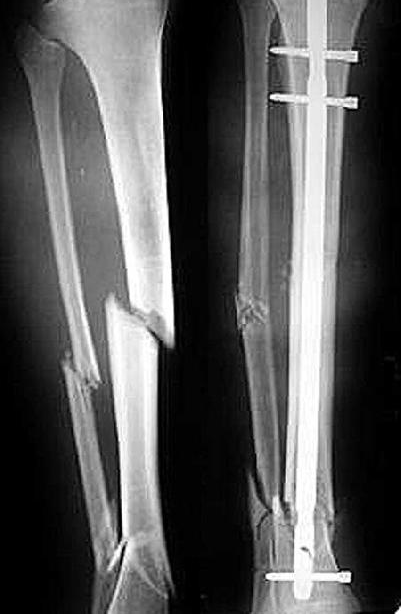

ПЕРЕЛОМ ЯКОЇ КІСТКИ І В ЯКІЙ ЇЇ ЧАСТИНІ ВИ БАЧИТЕ?

варіанти відповідей

ГОЛОВКИ HUMERUS

ДИСТАЛЬНОГО ЕПІФІЗА HUMERUS

ШИЙКИ FEMUR

ГОЛОВКИ FEMUR

ГОЛОВКИ RADIUS

ПРОКСИМАЛЬНОГО ЕПІФІЗА HUMERUS

ХІРУРГІЧНОЇ ШИЙКИ HUMERUS

АНАТОМІЧНОЇ ШИЙКИ HUMERUS